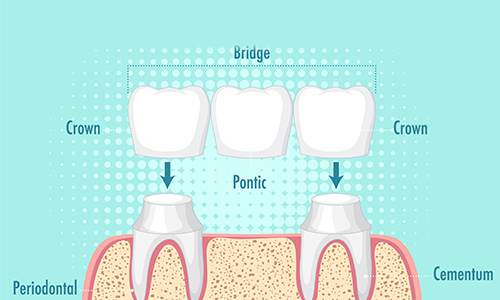

Crown, Bridges and Dentures